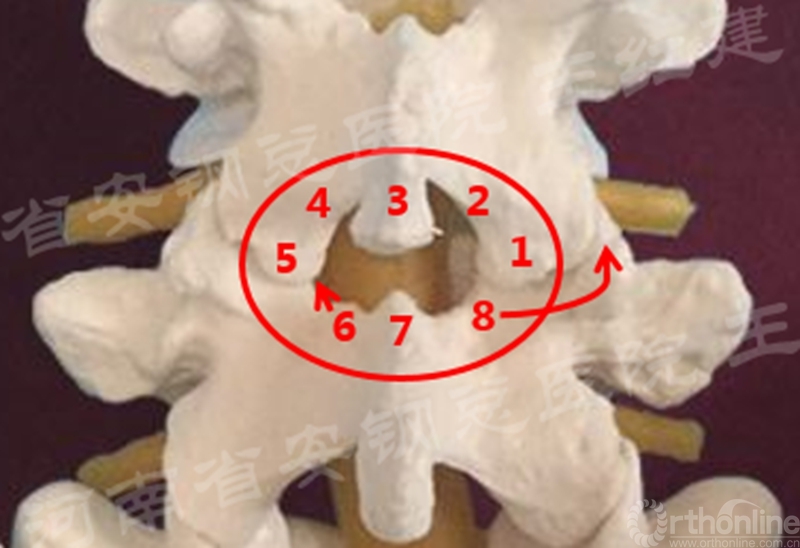

Endo-(P-T)LIF腰椎椎间融合技术四要点

二、镜下减压技术神经减压

(1)同侧椎管减压

在进行同侧椎管减压时,重点对侧隐窝及神经根管进行减压,操作中充分暴露上椎板黄韧带起点及下位椎板上5mm,去除肥厚的黄韧带、下关节突及上关节突增生部分。

(2)中央椎管减压

对于中央型狭窄的患者,应向内侧咬除黄韧带至棘突椎板交接处,再将工作通道管向对侧倾斜,将棘突基底部骨质的磨除。

(3)对侧椎板及侧隐窝的处理

在对侧椎板及侧隐窝的处理,潜行咬除对侧椎板深层,可用带保护套的高速小磨钻磨除椎板深层,即将对侧椎板磨薄,将椎管对侧部及对侧侧隐窝扩大成形,咬除对侧黄韧带至硬膜囊对侧外缘处与椎弓根处,根据对侧小关节突增生情况可用磨钻扩大对侧椎间孔与神经根管以解除对侧神经根压迫。

(4) 单侧入路双侧减压

置入内镜通道,用磨钻和枪钳切除上位椎板下缘、下位椎板上缘及突间关节内缘,切除黄韧带,完成单侧入路双侧减压。

单侧入路双侧减压的循序